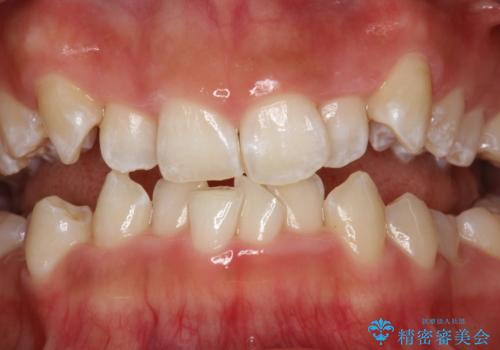

- 矯正治療前にステインを取りたいとのことで来院されました。ステインは前歯のみだったため、PMTC30分コースを行いました。

PMTCとは、歯科の専門家が器械を使用して行う歯のクリーニングのことです。普段の歯磨きでは取り切れない溝、キワなどの細かい部分も徹底的に除去します。ステインや歯石などが付着したままだと、虫歯や歯周病の発見がしずらいことがあります。特に矯正治療前には、念入りな虫歯や歯周病チェックが必要なため、PMTCでしっかりと汚れを除去しておくことが大切です。